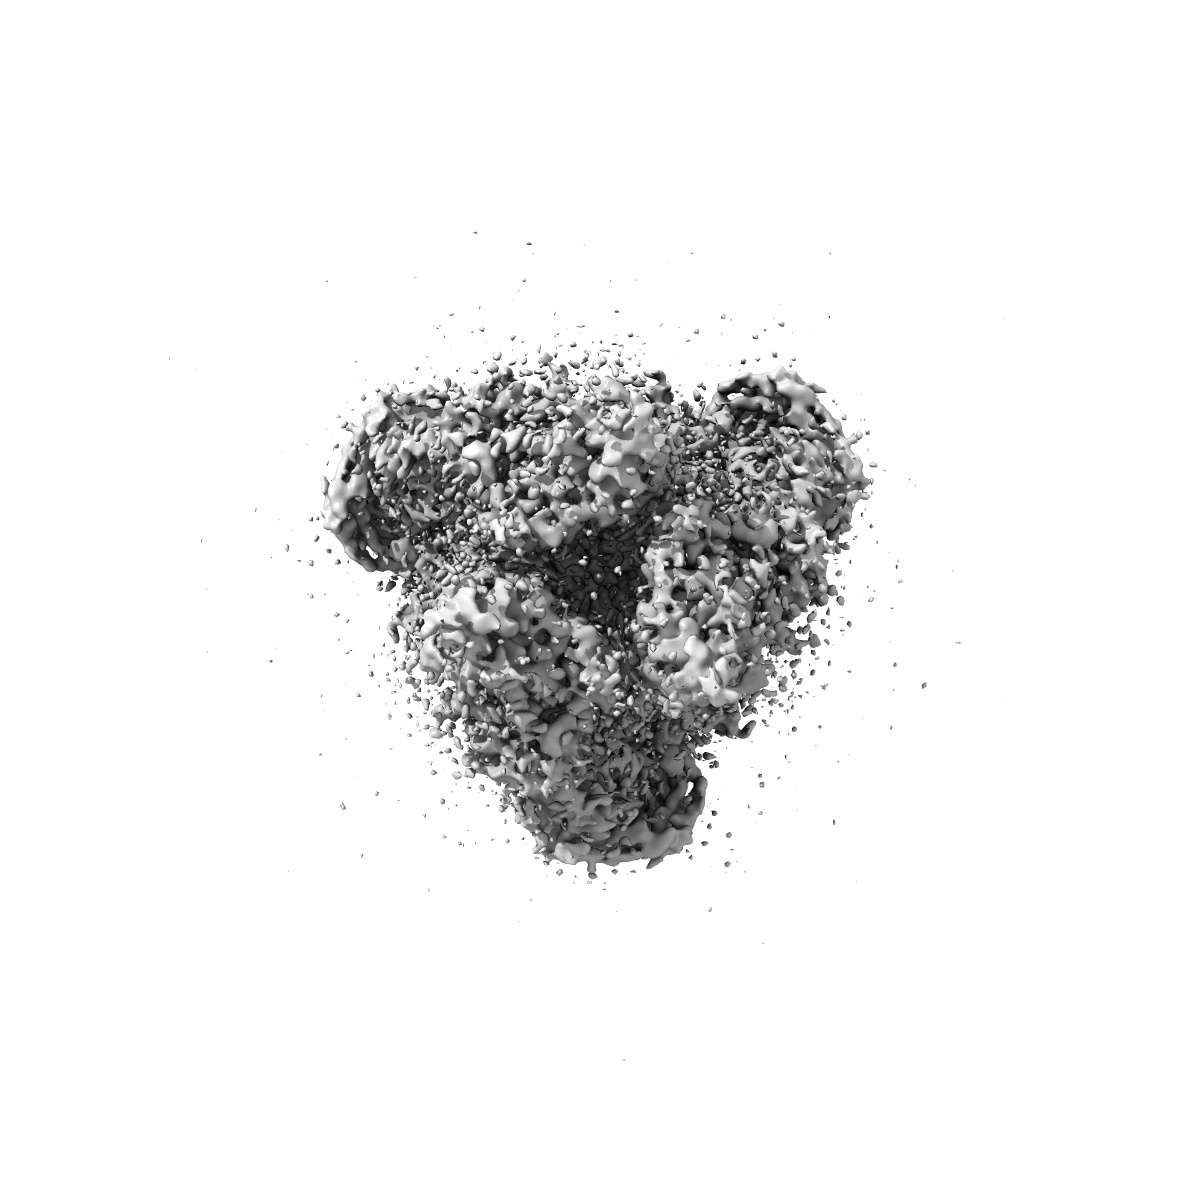

HSV-1 prefusion glycoprotein B

Single-particle2.64 Å

Sample: Human alphaherpesvirus 1 Glycoprotein B

A nanobody specific to prefusion glycoprotein B neutralizes HSV-1 and HSV-2.

(2025) Nature , 646 , 433 - 441